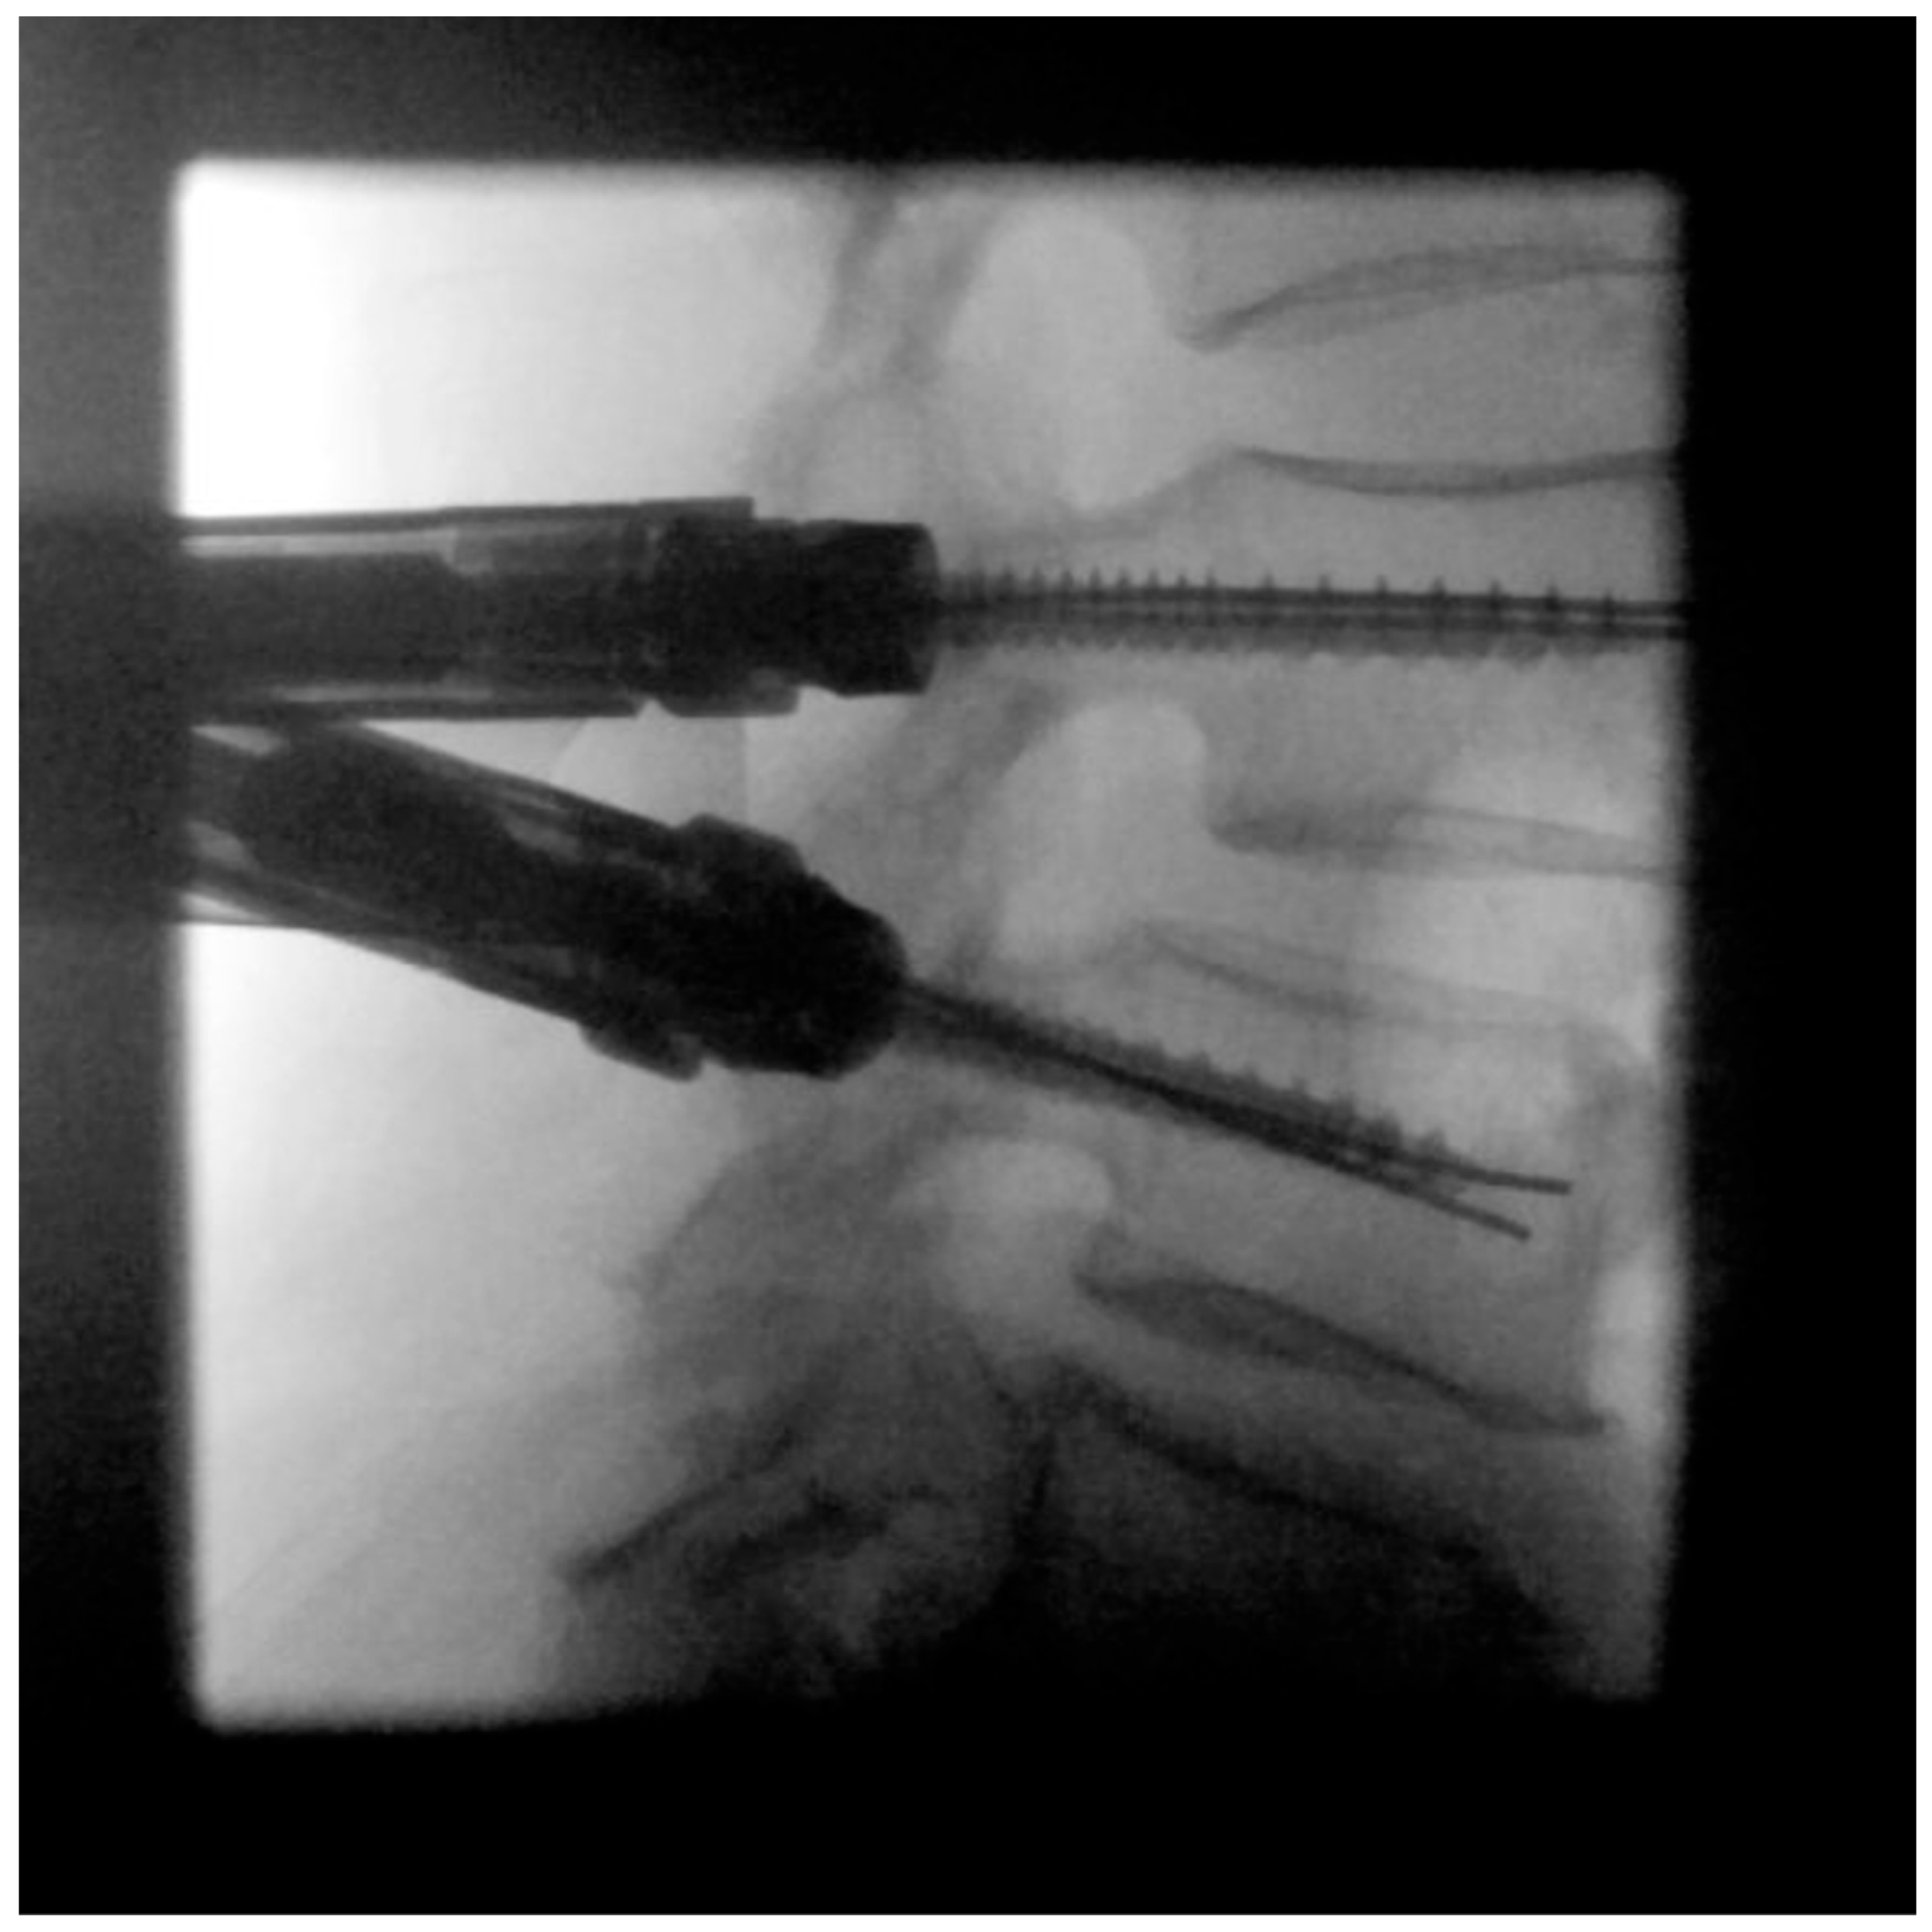

- Pedicle screw insertion

- Cage placement under lateral radiographic control

- MIS rod insertion using haptic feedback and no or very sparse lateral radiographic control